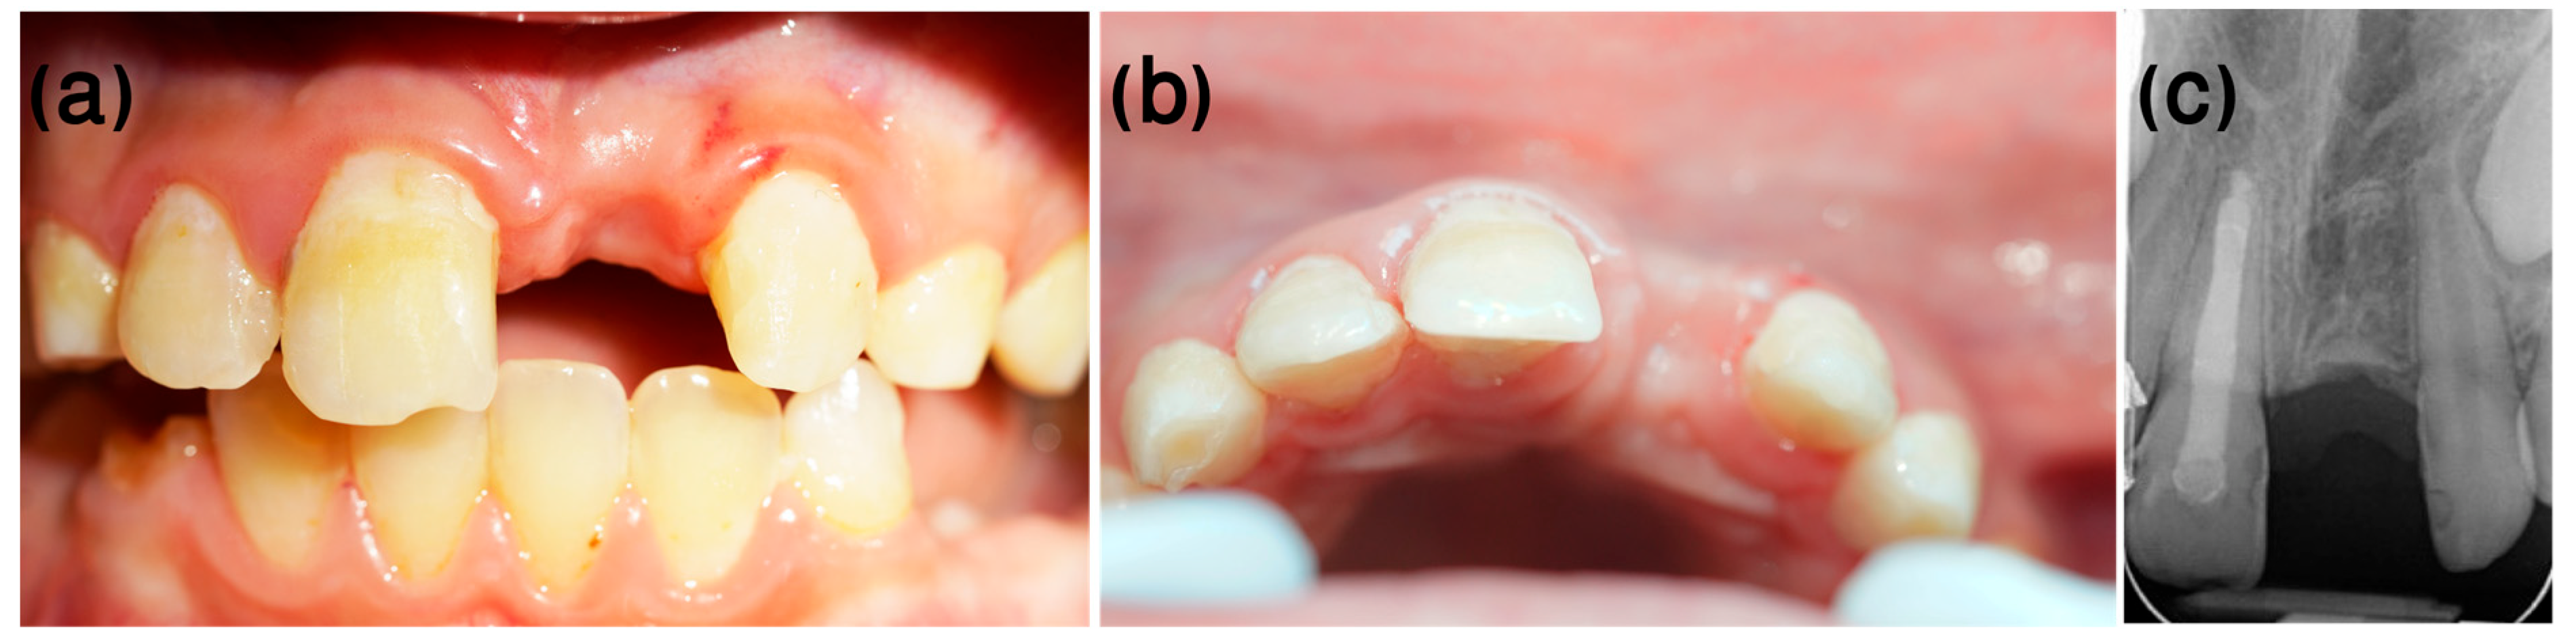

3.2. Case 2

- Dental history

- Clinical procedure

- Follow-up